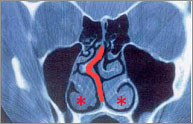

下の患者さんは、右に凸の鼻中隔彎曲症です(オレンジ太線)。また、特に左側に肥厚性鼻炎を認めます。

鼻腔の側壁から出ているヒダのようなものを下鼻甲介(上記写真の「*」部分)といいます。粘膜が厚かったり、骨がとび出ていたりすると肥厚性鼻炎になります。症状は、とにかく鼻が一日中詰まりっぱなしで、点鼻薬(血管収縮剤)もだんだんと効果がなくなってきます。これを直すのが、粘膜下下甲介骨切除術(とびでている骨を削る)、下鼻甲介粘膜切除術(厚くなった粘膜を削る)です。 いびき、睡眠時無呼吸との関連 睡眠時無呼吸とは、一晩(7時間)の睡眠中に10秒以上の無呼吸が30回以上おこる、または、睡眠1時間あたりの無呼吸数が5回以上おこることをいいます。そのため昼間の眠気など様々な症状が引き起こされます。睡眠中に無呼吸が繰り返され、体内の酸素不足、睡眠不足がおこります。その結果、日中の眠気、集中力、活力に欠けるなどの症状が現れます。仕事においてもその眠気のため重大事故を起こしやすくなります。鼻中隔彎曲症や肥厚性鼻炎はこの原因となることがあります。 手術の流れ - 鼻中隔矯正術 ※ 曲がっている部分の軟骨、骨だけをとりますので、鼻の高さが変わることはありません。